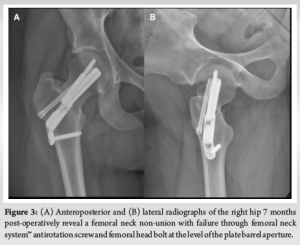

An active 21-year-old female sustained a right basicervical femoral neck fracture after being struck by a golf cart. She was treated at another institution using the FNS with an additional partially threaded headless screw (Fig. 2a and b). Seven months post-operatively, she developed progressive, atraumatic right hip pain with an inability to ambulate. She presented to our institution for evaluation. Radiographs demonstrated a right femoral neck non-union with implant failure through the bolt and antirotation screw at the level of the plate barrel aperture (Fig. 3a and b). She was consented for revision surgery with intertrochanteric valgus osteotomy and blade plate fixation.

We describe a case of FNS implant failure involving the antirotation screw and femoral head bolt, including a challenging removal and revision. It is important to alert surgeons to this failure mode, as it may impact pre-operative planning and implant selection. A multicenter case series of 125 patients treated with the FNS reported 2 cases (1.6%) of implant failure, but the failure sites were not specified [15]. In seven studies involving 473 FNS cases, no implant breakage was noted [16-22]. Several reports of FNS compromise exist in the FDA MAUDE database, though these often lack critical details and are not peer reviewed [23]. In this report, failure of both the bolt and the antirotation screw occurred where they exit from the plate barrel. In an analysis of SHS failure, the bending forces of the lag screw, analogous to the FNS bolt, increase along the implant from proximal to distal and reach a maximum at its intersection with the plate barrel [24]. In this case, that intersection occurred at, or very near, the patient’s fracture. Consequently, the shear forces at the fracture were concentrated near the point of maximal bending stress of the implant, likely contributing to failure at that location. Further, the bolt has an aperture on its superior surface, allowing for the antirotation screw to fit near its intersection with the plate barrel, which may have weakened the bolt and contributed to its failure at this level. The antirotation screw failed at the screw notch, placed at the same level as the end of the plate barrel, where the narrow caliber proximal third of the screw meets the larger caliber portion of the remaining screw. Biomechanically, this change in cross-sectional diameter may generate an area of stress concentration, which may have contributed to its failure at this location. In our case, the failed components were returned to the manufacturer for safety reporting in accordance with institutional protocol. We do not have access to a retrieval lab, and we did not receive a formal report or failure analysis from the manufacturer. In future cases, consultation with an implant retrieval laboratory may provide further insight into the failure mechanism and should be considered. In addition, no histopathological or advanced imaging analysis was performed on the resected bone. Such assessments may help characterize the biological integrity of bone at the failure site and its potential contribution to healing outcomes or implant performance. Beyond implant design, the patient’s non-union resulted in prolonged reliance on and loading of the implant. In a study of non-geriatric patients with femoral neck fractures treated with the FNS, the mean time to union was 2.86 months ±0.77, with 2 patients developing non-union [18]. Reported non-union rates for patients treated with FNS range from 1 to 10% [15,17,18,20-22]. Known risk factors for femoral neck non-union include high fracture angle (i.e., Pauwels Type III), initial fracture displacement, and inadequate reduction [2,25-29]. This patient had a displaced fracture (Garden IV) with a fracture angle of 48°, near the cut-off for a Pauwels Type III (50°). Of note, original injury films and intraoperative imaging from the index surgery were unavailable, limiting full assessment of reduction quality and fracture characteristics. However, initial post-operative imaging revealed a slight residual fracture gap inferomedially, which may have limited compression (Fig. 2a). Therefore, in a healthy patient without risk factors for non-union, the initial and non-anatomic reduction may have contributed to non-union and implant failure. While the fracture was reduced in slightly more valgus, post-operative imaging, as well as the operative report, revealed no evidence of implant malposition or mechanical error. Although it is not possible to confirm whether the implant was fully tightened at the time of surgery, the simultaneous failure of both the antirotation screw and bolt at the non-union site suggests fatigue loading as the likely mechanism. In a study of femoral neck non-union, 7 of 9 cases of non-union in patients with fixed-angle devices occurred in the setting of uncontrolled collapse and loss of bone stock [30]. Interestingly, in this case, there was relatively well-preserved bone stock and minimal femoral neck shortening along the line of the FNS bolt. In biomechanical studies, the FNS has performed similarly to SHS and superior to cannulated screws [9-11,31,32]. However, a single study found that cannulated screws have better biomechanical stability in fractures with non-anatomic reductions [33]. In clinical studies, the FNS has shown lower complication rates compared to cannulated screws and similar outcomes to SHS [16,18,19,21]. Compared to a SHS, the FNS is reported to be less invasive with a smaller incision, shorter operative time, and less blood loss [12]. High rates of non-union can be expected when treating displaced femoral neck fractures, and surgeons who use the FNS device should be aware of the possibility that this device could fail in the manner we describe, should non-union occur, rendering implant removal difficult [34-36]. We recognize that this report describes a single patient experience, which precludes generalizations about overall device reliability, and we do not suggest the FNS is uniquely failure-prone; any device can fail in a non-union under mechanical stress. However, this failure mode presented unusual technical challenges during revision, particularly in comparison to more commonly used constructs, which surgeons should be aware of during surgical planning. The need for trephination to extract the broken antirotation screw and the use of a threaded Steinmann pin to retrieve the broken bolt added complexity and required careful preservation of limited bone stock. These technical demands alone prolonged the surgery by approximately 60 min. The resulting bone loss and surgical burden underscore the importance of considering potential revision implications during implant selection, especially in fractures with relatively high complication rates, such as displaced femoral neck fractures. This consideration is particularly salient in young, active patients, where implant durability, the demands of high-impact activity, and the feasibility of future revisions are critical concerns. Studies have highlighted that younger patients with femoral neck fractures face a unique treatment dilemma—balancing the need for stable fixation against the long-term risk of mechanical failure and reoperation, including conversion to arthroplasty [37,38]. Beyond technical complexity, revision procedures following femoral neck implant failure can impose substantial healthcare and societal costs. Studies have shown that revision surgery after failed internal fixation is associated with significantly higher overall costs and resource utilization compared to primary fixation or arthroplasty [39]. While we did not quantify cost in this case, the surgical demands and resource intensity of osteotomy and blade plate fixation underscore the importance of pre-operative planning and appropriate implant selection to minimize the risk and burden of revision. In addition, while our patient achieved a full return to activity, we did not obtain standardized functional outcome scores, such as the Harris hip score or SF-36 during follow-up. Incorporating validated outcome measures in future case reports and studies would strengthen objective assessments of recovery.